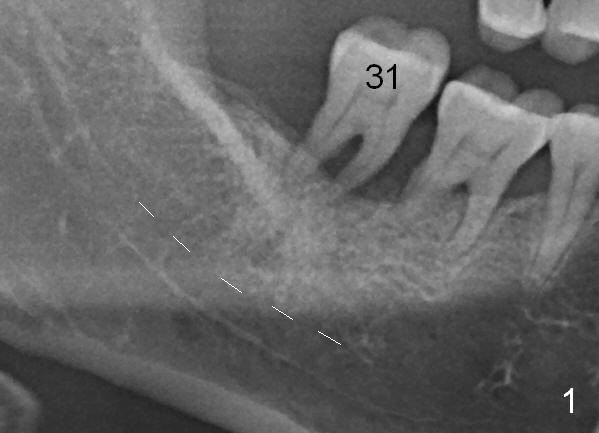

A 46-year-old lady has generalized moderate localized severe (Fig.1 (panorex) #31) chronic periodontitis.  Surprisingly there is sufficient bone height (Fig.1 white dashed line: upper border of the Inferior Alveolar Canal).  The gingiva is quite thick (Fig.2 (PA) arrowheads: gingival margin).  In order to prevent thread exposure associated with immediate implant, a bone-level implant will be placed (Fig.3 5.3x8 mm; green lines) with a long abutment (5.8x5.5 mm (black lines) (6 mm cuff; red lines)).   Initial osteotomy depth is between 14 and 17 mm.  Insert a parallel pin and take the 1st intraop PA.  Use reamers to enlarge osteotomy and collect autogenous bone.  A drill with a stopper (5x8mm) will be used prior to placement of the implant mentioned above.  Since the opposing is a removable partial denture, an immediate provisional at the site of #31 should be safe to be fabricated.  Bone graft will be placed to cover the exposed implant surface.  The remaining gap will be filled with collagen dressing and the provisional.  A temporary abutment is the other option.  The shoulder of the temporary abutment will be subgingival to long extent.  Is the plan well executed?